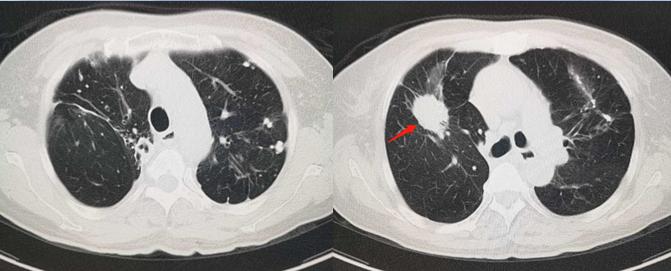

59岁男性,间断咳嗽,咳痰两年:

CT发现双上肺多发病灶,考虑肺结核,建议做个增强扫描排除肿瘤,支气管镜检查也有必要。

结果,同时查到结核杆菌和鳞癌细胞。

这是一位肺结核患者,同时合并肺鳞癌。

已经手术好多年了,还活着!

这个支气管镜检查,是多余检查吗?不是!